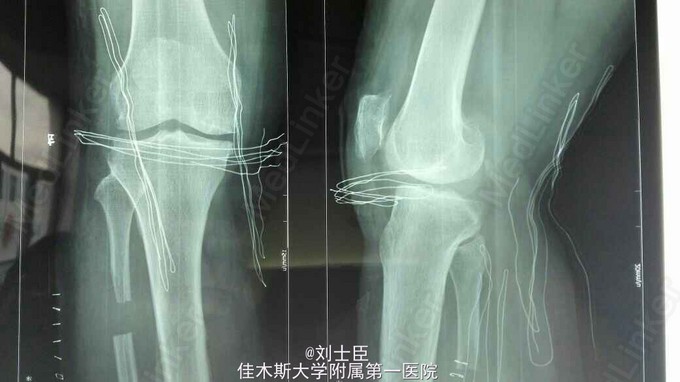

xx,女,54岁。左膝疼痛伴活动受限5年加重1个月。上下楼困难,走平路500米跛行。

左膝内侧压痛明显,伸直10度,屈曲100度。蹲起困难。过伸过曲实验阳性。

左膝关节骨性关节炎。 膝关节镜清理术加腓骨截骨术。

病人术后疼痛减轻,行走自如。蹲起良好。伸直5度,屈曲120度。平路和上下楼疼痛减轻。 术后4周膝关节轻度肿胀。症状体征进一步好转。能长时间行走,间断上下楼。 您对此种做法的观点?同意或不同意。 您对此病的治疗观点?您通过自己的治疗方法,患者的满意率如何? 您是否会选择膝关节置换?您有把握让假体生存20年或更长,而患者满意吗?